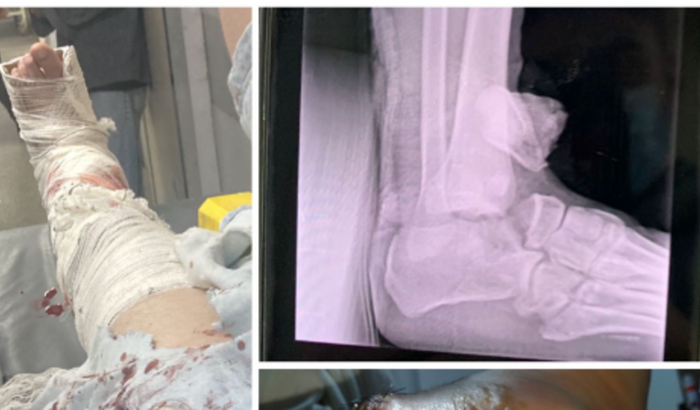

Olá amigos, venho através desta vaquinha pedir ajuda, sofri um acidente no dia 06.11.2022 onde um carro cortou minha preferencial e acabei tendo uma fratura exposta no tornozelo esquerdo. Hoje 24.11.2022 data do meu retorno a traumatologia da santa casa tive o diagnóstico de grande risco de perder o movimento do pé e precisarei fazer tratamento onde o custo com remédios será bem alto, além de também ter que fazer fisioterapia que terá outro alto custo, infelizmente quem causou o acidente simplesmente não arcou com nenhum dos custos que tive até então e nem se prestou a dar nenhuma assistência. Até a data de hoje já tive um custo de R$ 1000,00 com medicamentos e cuidados, vou ter mais o custo do novo tratamento em torno de R$ 2000,00 e a fisioterapia custaria a partir de R$ 4500,00, esta podendo ter um custo maior em caso de necessidade de tratamento por um tempo maior.